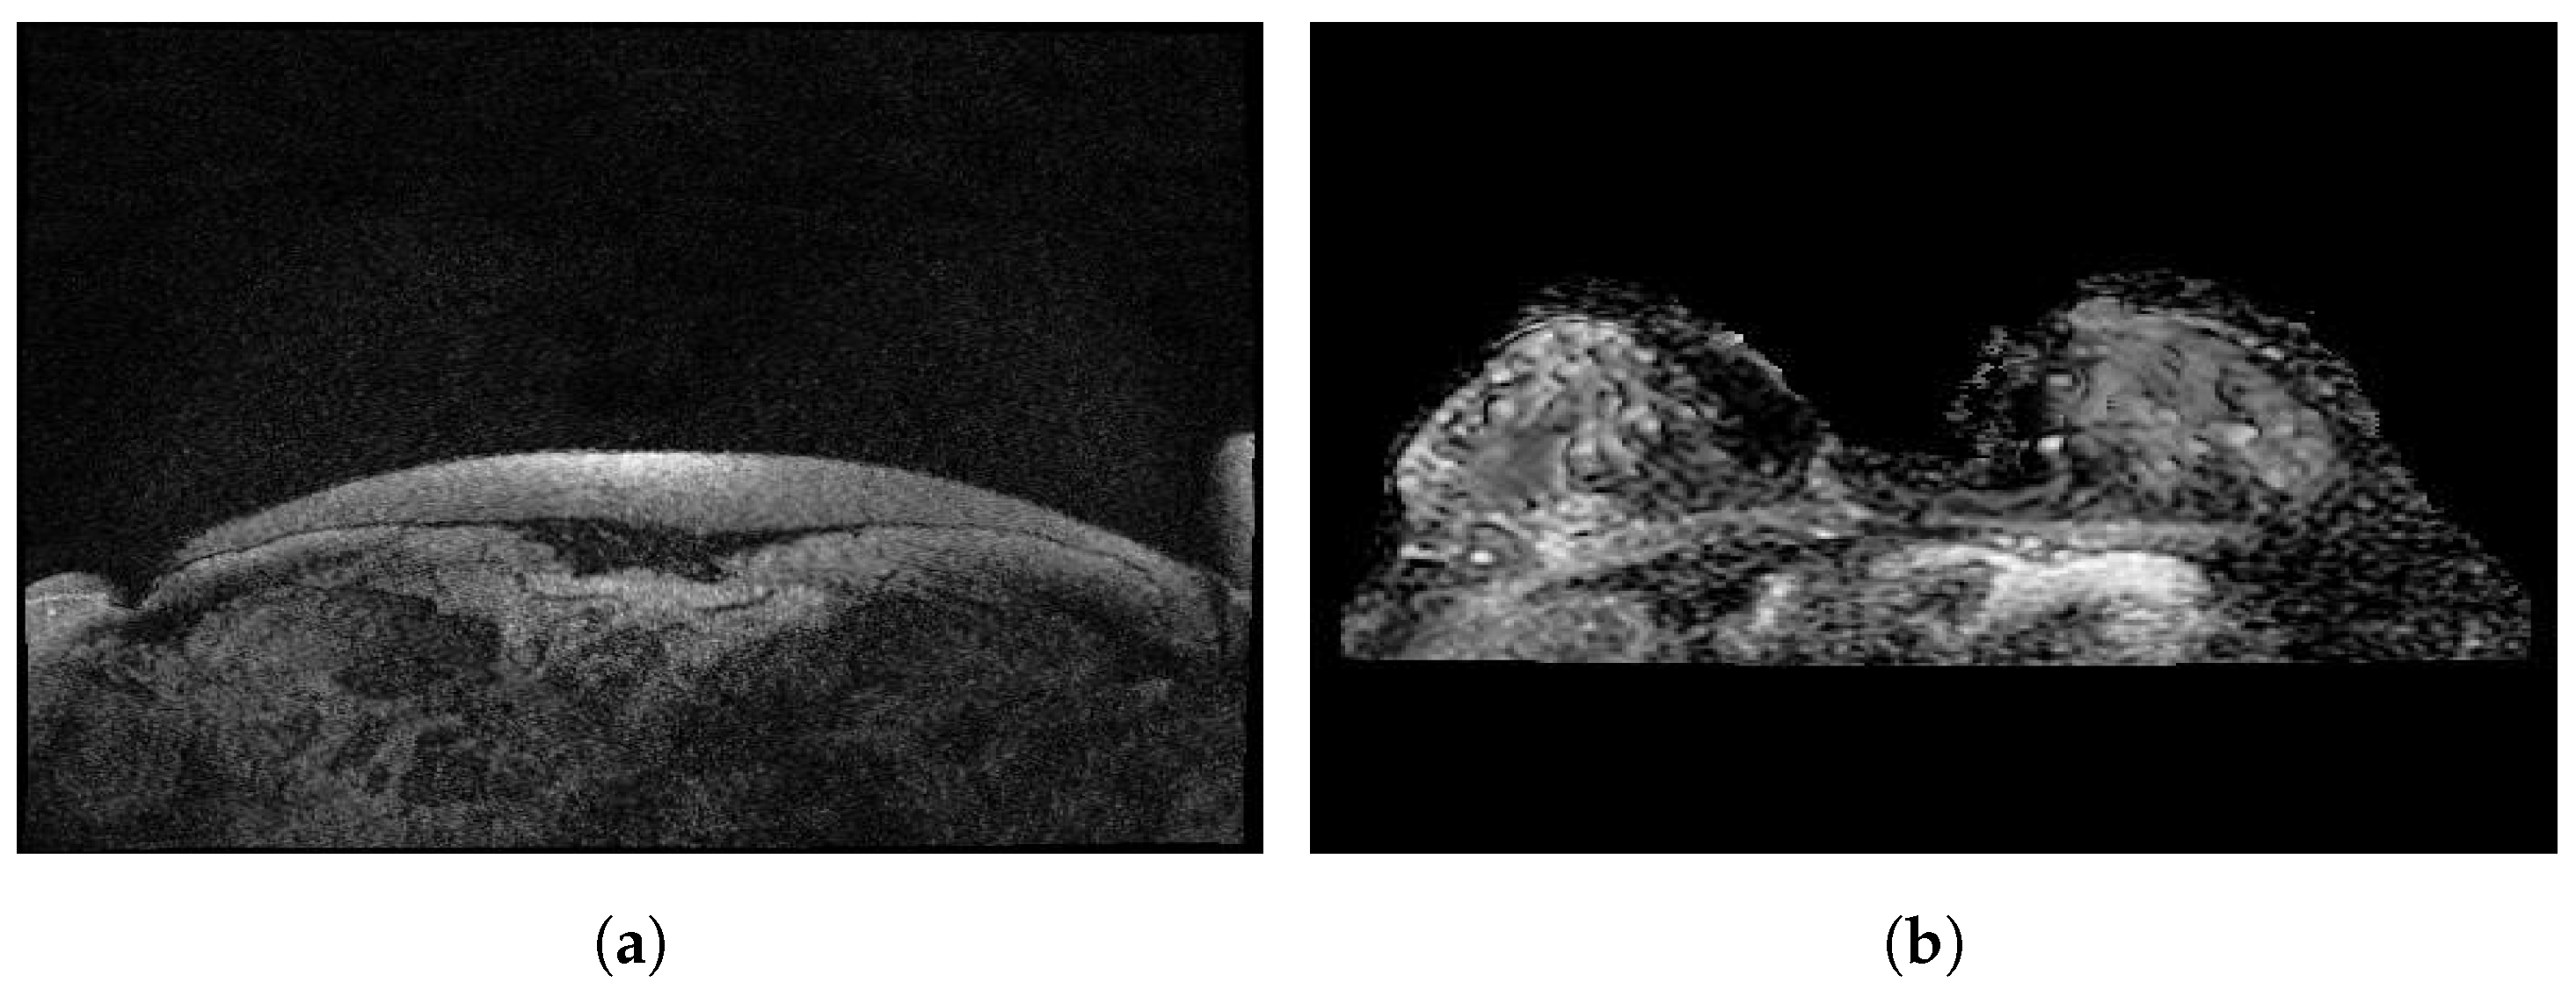

3.9. DMR-Database for Mastology Research-Visual Lab

The DMR-Database [24] has been collected since 2010 by the Database for Mastology Research-Visual Lab, UFF, Niteroi, Brazil. This dataset was taken by FLIR SC-620 thermal cameras with 480 × 640 pixel resolution. Static and dynamic protocols were used to acquire the images. Static images are recorded after 10 to 15 min of thermal stabilization while the patient rested. However, the dynamic images are comprised of a sequence of thermograms taken every 15 s during five minutes. Static protocols reduce the formation of false regions of warmth or cold by uniformly cooling the skin of the breasts and armpits. However, there is a long resting time needed to stabilize skin temperature. A total of 5760 images are divided into 3 classes, healthy, sick, and unknown, and are available in JPG format. Figure 4 illustrates some sample static and dynamic images from the DMR-Database.